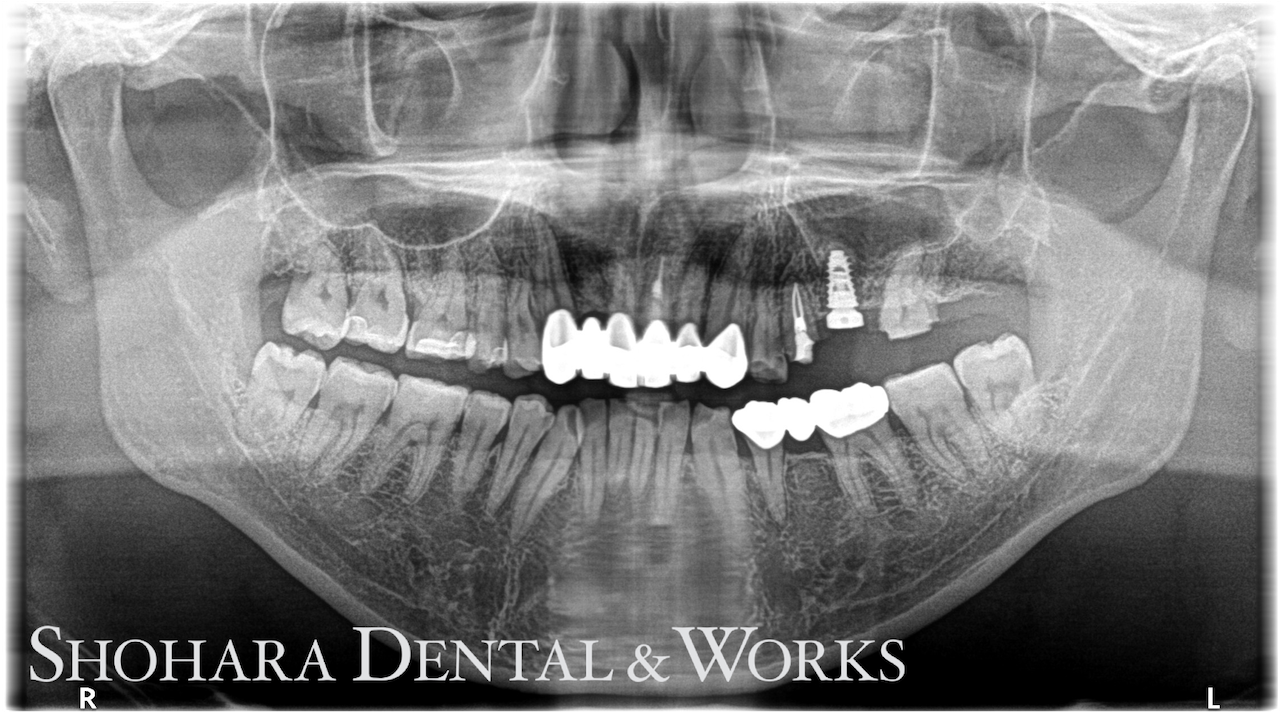

インプラント手術後のレントゲン写真

左上欠損部はCT撮影して診断した結果、骨の高さが5mmほどで8.5mmのインプラントを埋入するには骨高が足りませんでした。

よって、サージカルステントを作製し、フラップレスにてソケットリフトで骨造成を行いました。

また、初期固定が十分だったため、当日口腔内スキャナーで印象採得も行いました。